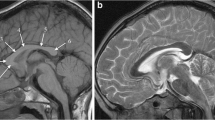

Reduced blood supply or oxygen delivery around the time of birth is often termed “birth asphyxia” and is a cause of neonatal encephalopathy. In some cases there is lasting brain injury visible on MR imaging, usually in children who have sustained moderate or severe hypoxia/ischaemia. The pattern of such hypoxic–ischaemic brain injury on subsequent brain MR imaging studies depends on several factors, but most important are the gestational maturity and the severity and duration of the hypoxic–ischaemic event. Children with hypoxic–ischaemic brain injury who are born at or near term (37 weeks or more) usually have one of two patterns of injury. If the hypoxic–ischaemic event is short-lasting (10–25 min) but severe (e.g., following uterine rupture) the injury tends to involve the basal ganglia, thalami and paracentral lobules and is called acute profound hypoxic–ischaemic brain injury (Fig. 1) [1]. If the hypoxic–ischaemic event is more prolonged, with less severe reduction in blood supply or oxygen delivery (e.g., incomplete placental abruption) the parasagittal watershed regions of the cerebral hemispheres tend to be injured and this is called prolonged partial hypoxic–ischaemic brain injury [1]. Mixed patterns of acute profound and prolonged partial hypoxic–ischaemic brain injury can occur. Children affected by either of those injuries are likely to incur some form of cerebral palsy.

MR images in a 6-year old boy with dyskinetic cerebral palsy who has the typical neuroimaging findings of acute profound hypoxic–ischaemic brain injury. a, b Axial T2-weighted MR images at the level of the basal ganglia (a) and peri-rolandic cortex (b) show gliosis and reduction in volume of the putamina (open arrows), thalami and paracentral lobules (solid arrows). c A mid-sagittal T1-weighted MR image shows a focal reduction in thickness in the posterior part of the body of the corpus callosum (arrows)

Acute profound hypoxic–ischaemic brain injury can occur secondary to severe cerebral hypoperfusion as might result from uterine rupture, for example. The resulting severe hypoxia–ischaemia tends to produce selective damage to the parts of the brain with the highest metabolic demands (probably reflecting ongoing myelination rather than neuronal activity). As such, the typical pattern of injury seen on MR imaging involves the basal ganglia and thalami and explains why dyskinetic cerebral palsy is a frequent clinical outcome. Other regions of the brain are involved, however, including the paracentral lobules, which contain the primary motor and sensory cortices and their afferent and efferent connections (Fig. 1).